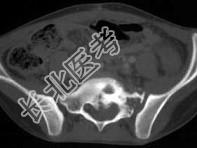

- 单项选择题如图所示,该青少年的最可能的诊断是 ( )

A、尤文肉瘤

B、淋巴瘤

C、软骨肉瘤

D、转移瘤

E、骨肉瘤